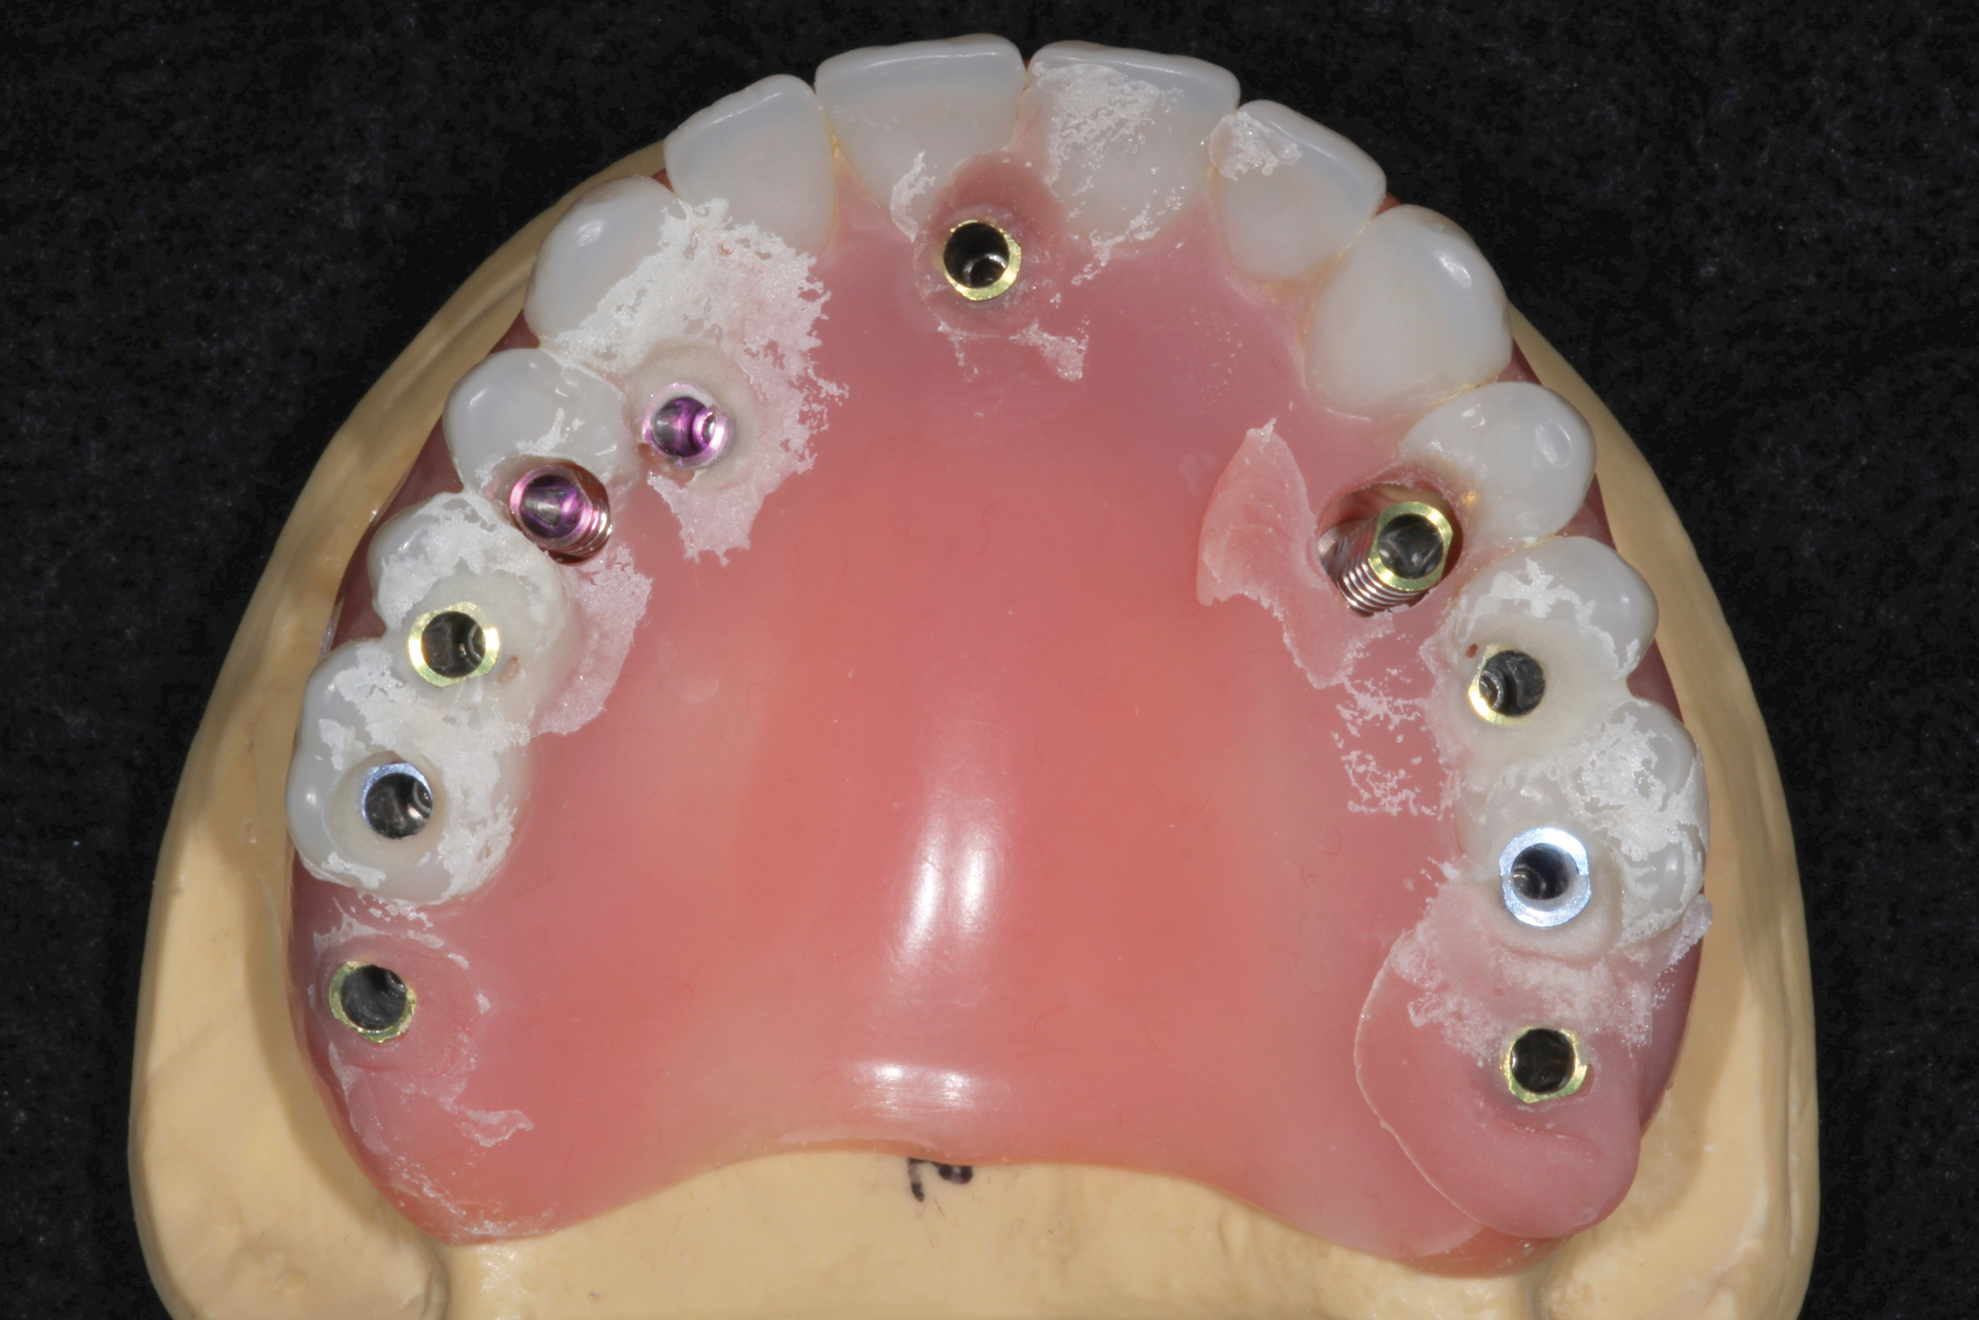

Fig 13. Digital planning of definitive restoration.

13

Figure 13